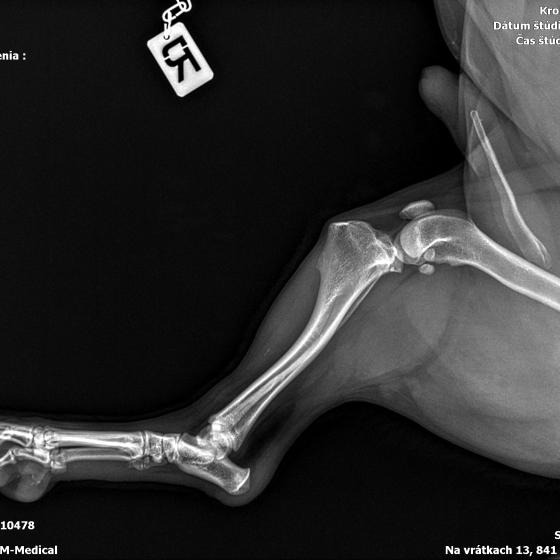

Karola nám doviezla pani, ktorá ho našla, asi jediná dobrá duša, ktorá pri ňom neprešla so zatvorenými očami. Ihneď sme s krpcom utekali na veterinu aby sa zistila závažnosť jeho zranení. Hneď pri prvých RTG snímkoch sa ukázala obojstranná fraktúra panvy, taktiež fraktúra krídla panvy a keby mu to chudákovi nestačilo, do tretice sa objavila zlomenina stavca. Karolko mal neznesiteľné bolesti, ale krásne prečkal vyšetrenie lebo vedel, že je v dobrých rukách a dostáva sa mu pomoci. Po nálezoch sme okamžite kontaktovali neurológiu a ortopédiu na veterinárnej klinike Sibra - centrum veterinárnej medicíny, kde sme dostali hneď termín na príjem.

S obrovskou radosťou sme počúvali slová neurológa, MVDr. Hájeka keď nám oznámil, že...

Karol nemá žiadne neurologické deficity, po ortopedickej operácii bude vedieť behať a bez problémov bude vedieť samostatne cikať a kakať. Po tejto úžasnej správe sme samozrejme dali zelenú náročnej ortopedickej operácii pod vedením MVDr. Vatolíka. Operácia sa podarila na výbornú, Karči je "zoskrutkovaný" a vôbec nič mu nebráni v tom, aby opäť mohol behať a aktívne žiť. Momentálne sa zotavuje po operácii, musí mať prísny kľudový režim. Po vybratí stehov ho čaká hydro- a fyzioterapia, ktorá mu pomôže postaviť sa na nohy. Je to bojovník, veľmi sa chce uzdraviť a v jeho očkách je dokonale vidieť, že už kuje plány čo všetko zameškané bude musieť dobehnúť.